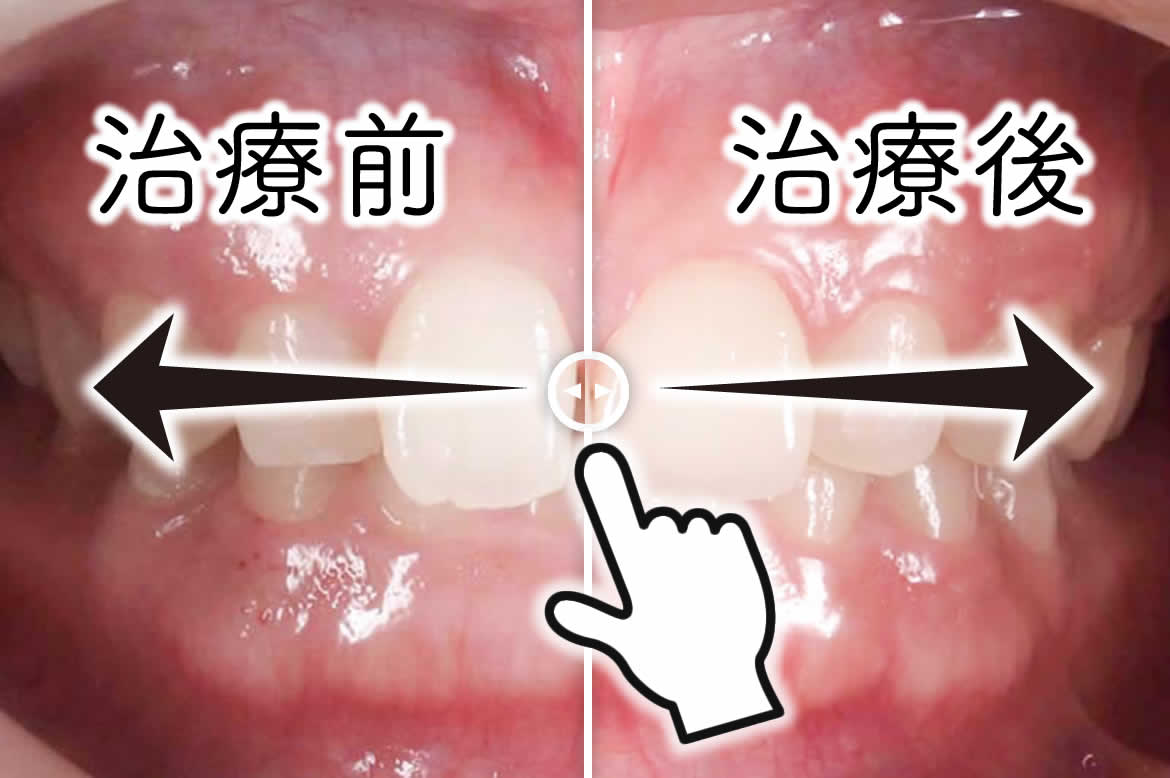

症例画像のご覧方法

画像中央の白線を指で左右に動かすことで、治療前後の様子をご覧いただけます。